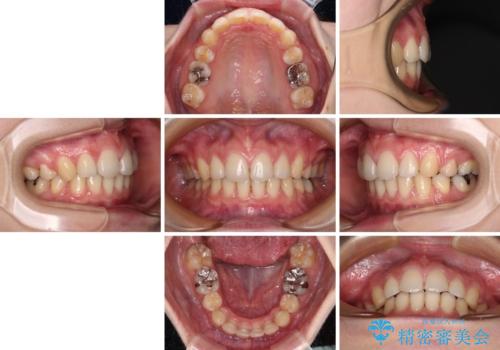

- 口元の突出感と口の閉じにくさを気にして来院された患者様です。

上下左右第一小臼歯4本を抜歯し、ワイヤー装置にて口元を引っ込めるよう矯正治療を行うこととしました。

ご友人などがびっくりするほど口元の突出感を改善することができ、患者様には大変満足していただきました。